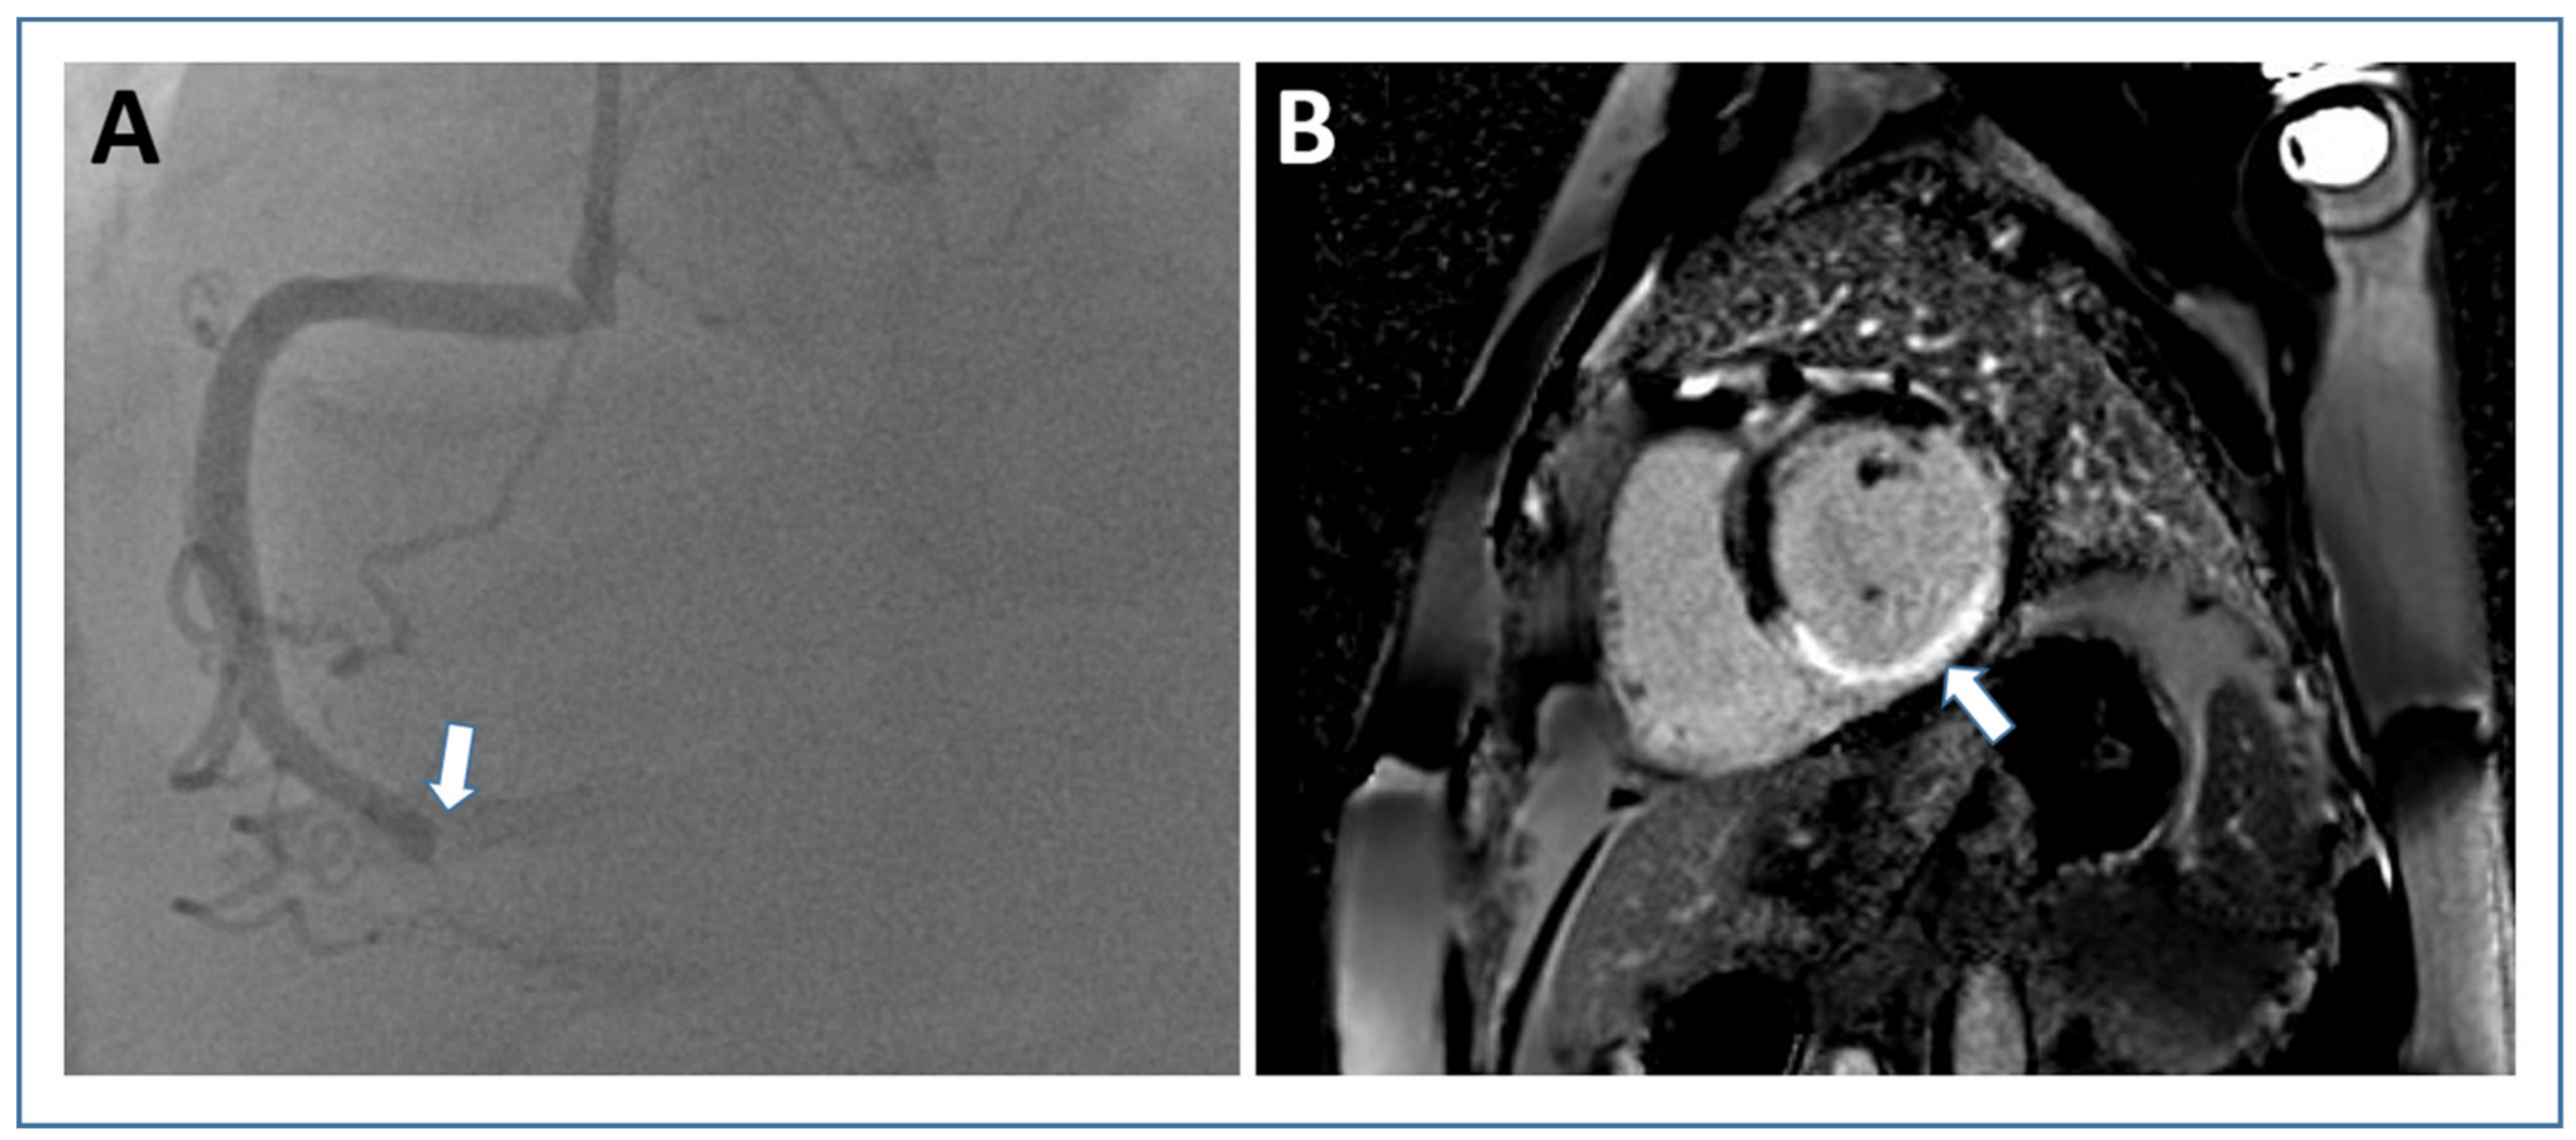

7. Left Ventricular Thrombus

- Bulluck, H.; Chan, M.H.H.; Paradies, V.; Yellon, R.L.; Ho, H.H.; Chan, M.Y.; Chin, C.W.L.; Tan, J.W.; Hausenloy, D.J. Incidence and predictors of left ventricular thrombus by cardiovascular magnetic resonance in acute ST-segment elevation myocardial infarction treated by primary percutaneous coronary intervention: A meta-analysis. J. Cardiovasc. Magn. Reson. 2018, 20, 72. [Google Scholar] [CrossRef]

- Poss, J.; Desch, S.; Eitel, C.; de Waha, S.; Thiele, H.; Eitel, I. Left Ventricular Thrombus Formation after ST-Segment-Elevation Myocardial Infarction: Insights from a Cardiac Magnetic Resonance Multicenter Study. Circ. Cardiovasc. Imaging 2015, 8, e003417. [Google Scholar] [CrossRef] [PubMed]